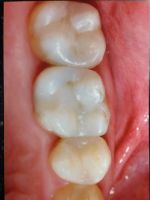

Onlays and Inlays

Before

After